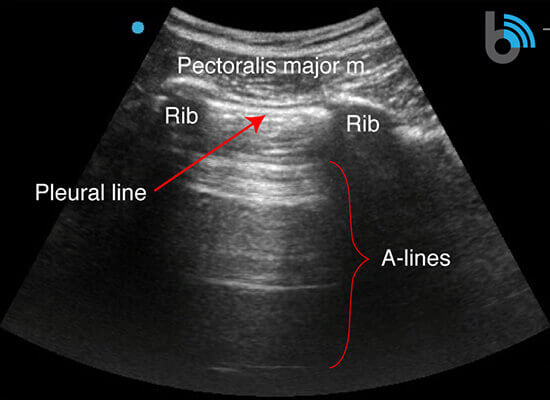

Anatomy

- The ribs will appear as convex hyperechoic lines with acoustic shadows.

- Located between the ribs are the hypoechoic intercostal muscles and the smooth, thin hyperechoic pleural line.

- These structures form the “bat sign”: the shadow of the ribs form the wings, while the area between the ribs represents the body.

A-lines

- Hyperechoic, horizontal reverberation artifacts.

- Equally spaced

- Extend below the pleural line.

- Subpleural air (due to alveolar air or pneumothorax) creates a large difference in acoustic impedance at the interface between the chest wall and the air filled alveoli.

- Sound waves will reflect between the transducer and pleura several times, producing the repetitive lines.

- The appearance of A-lines indicates the presence of subpleural air, but does not differentiate between alveolar air (normal lung) and pleural air (pneumothorax).

- A-lines in the presence of lung sliding indicate alveolar air and not a pneumothorax.

- A-lines in the absence of lung sliding may indicate a pneumothorax, but requires additional findings (i.e. lung point).